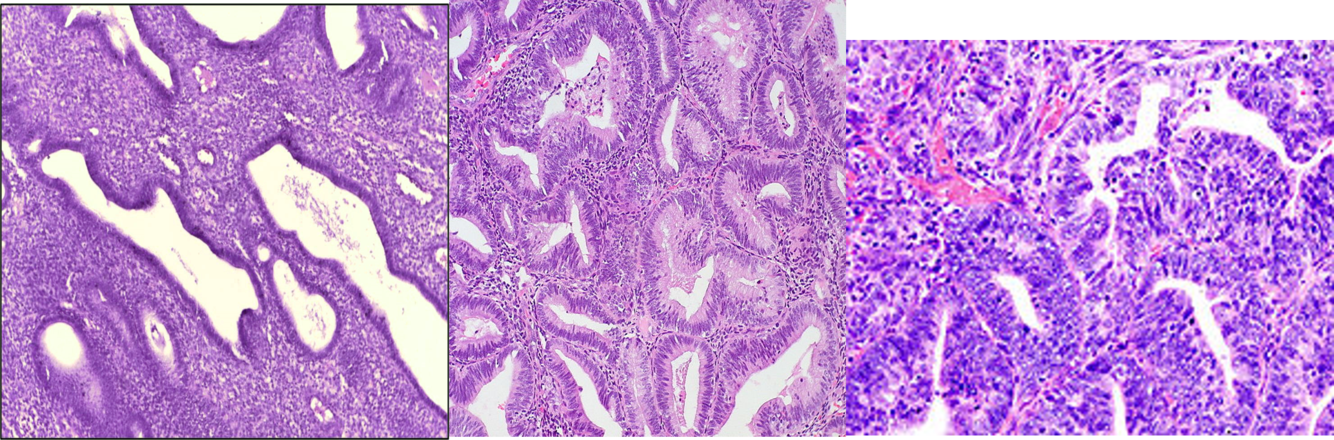

Label the types of endometrial hyperplasia shown

from left to right goes, simple, complex and then atypical hyperplasia